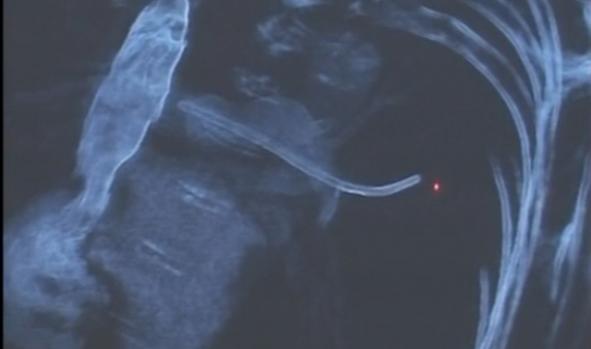

I-au extras din plaman un obiect lung de aproape 10 cm | Imaginea 1 din 2 | Galerie Foto

I-au extras din plaman un obiect lung de aproape 10 cm I-au extras din plaman un obiect lung de aproape 10 cm